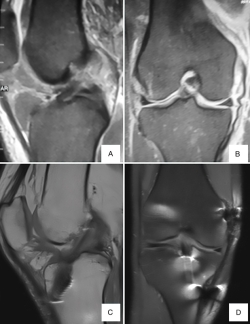

Figura 2. Resonancia magnética correspondiente a paciente de 23 años con lesión asociada de ligamento cruzado anterior (LCA) y ligamento colateral medial (LCM) de grado III. A y B: resonancia preoperatoria donde se observa lesión completa del LCA (A) y lesión de LMC de grado III proximal (B).